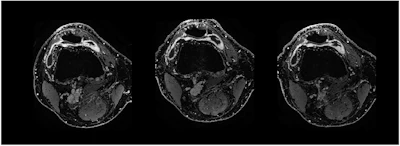

Contrast-enhanced T1 weSPGR images of the knee of a patient from the GAE group at the level of the suprapatellar recess. The baseline image (left) shows a marked synovial enhancement. There was no change one month after treatment (middle image) and four months after treatment (right image).European Radiology

The finding is from a comparison among 58 participants with mild to moderate knee osteoarthritis who were unresponsive to conservative treatment, and further found no MRI differences between the groups in synovitis reduction, noted lead author Tijmen van Zadelhoff, MD, of Erasmus MC in Rotterdam, the Netherlands, and colleagues.

Participants received either GAE (n = 29) or a sham procedure (n = 29) in which a groin incision was made and all procedural steps were mimicked without actual embolization. Follow-up visits were conducted at one, four, eight, and 12 months. Pain was assessed using the Knee Injury and Osteoarthritis Outcome Score (KOOS) [range, zero to 100], and synovitis was evaluated with contrast-enhanced MRI at baseline, one month, and four months.